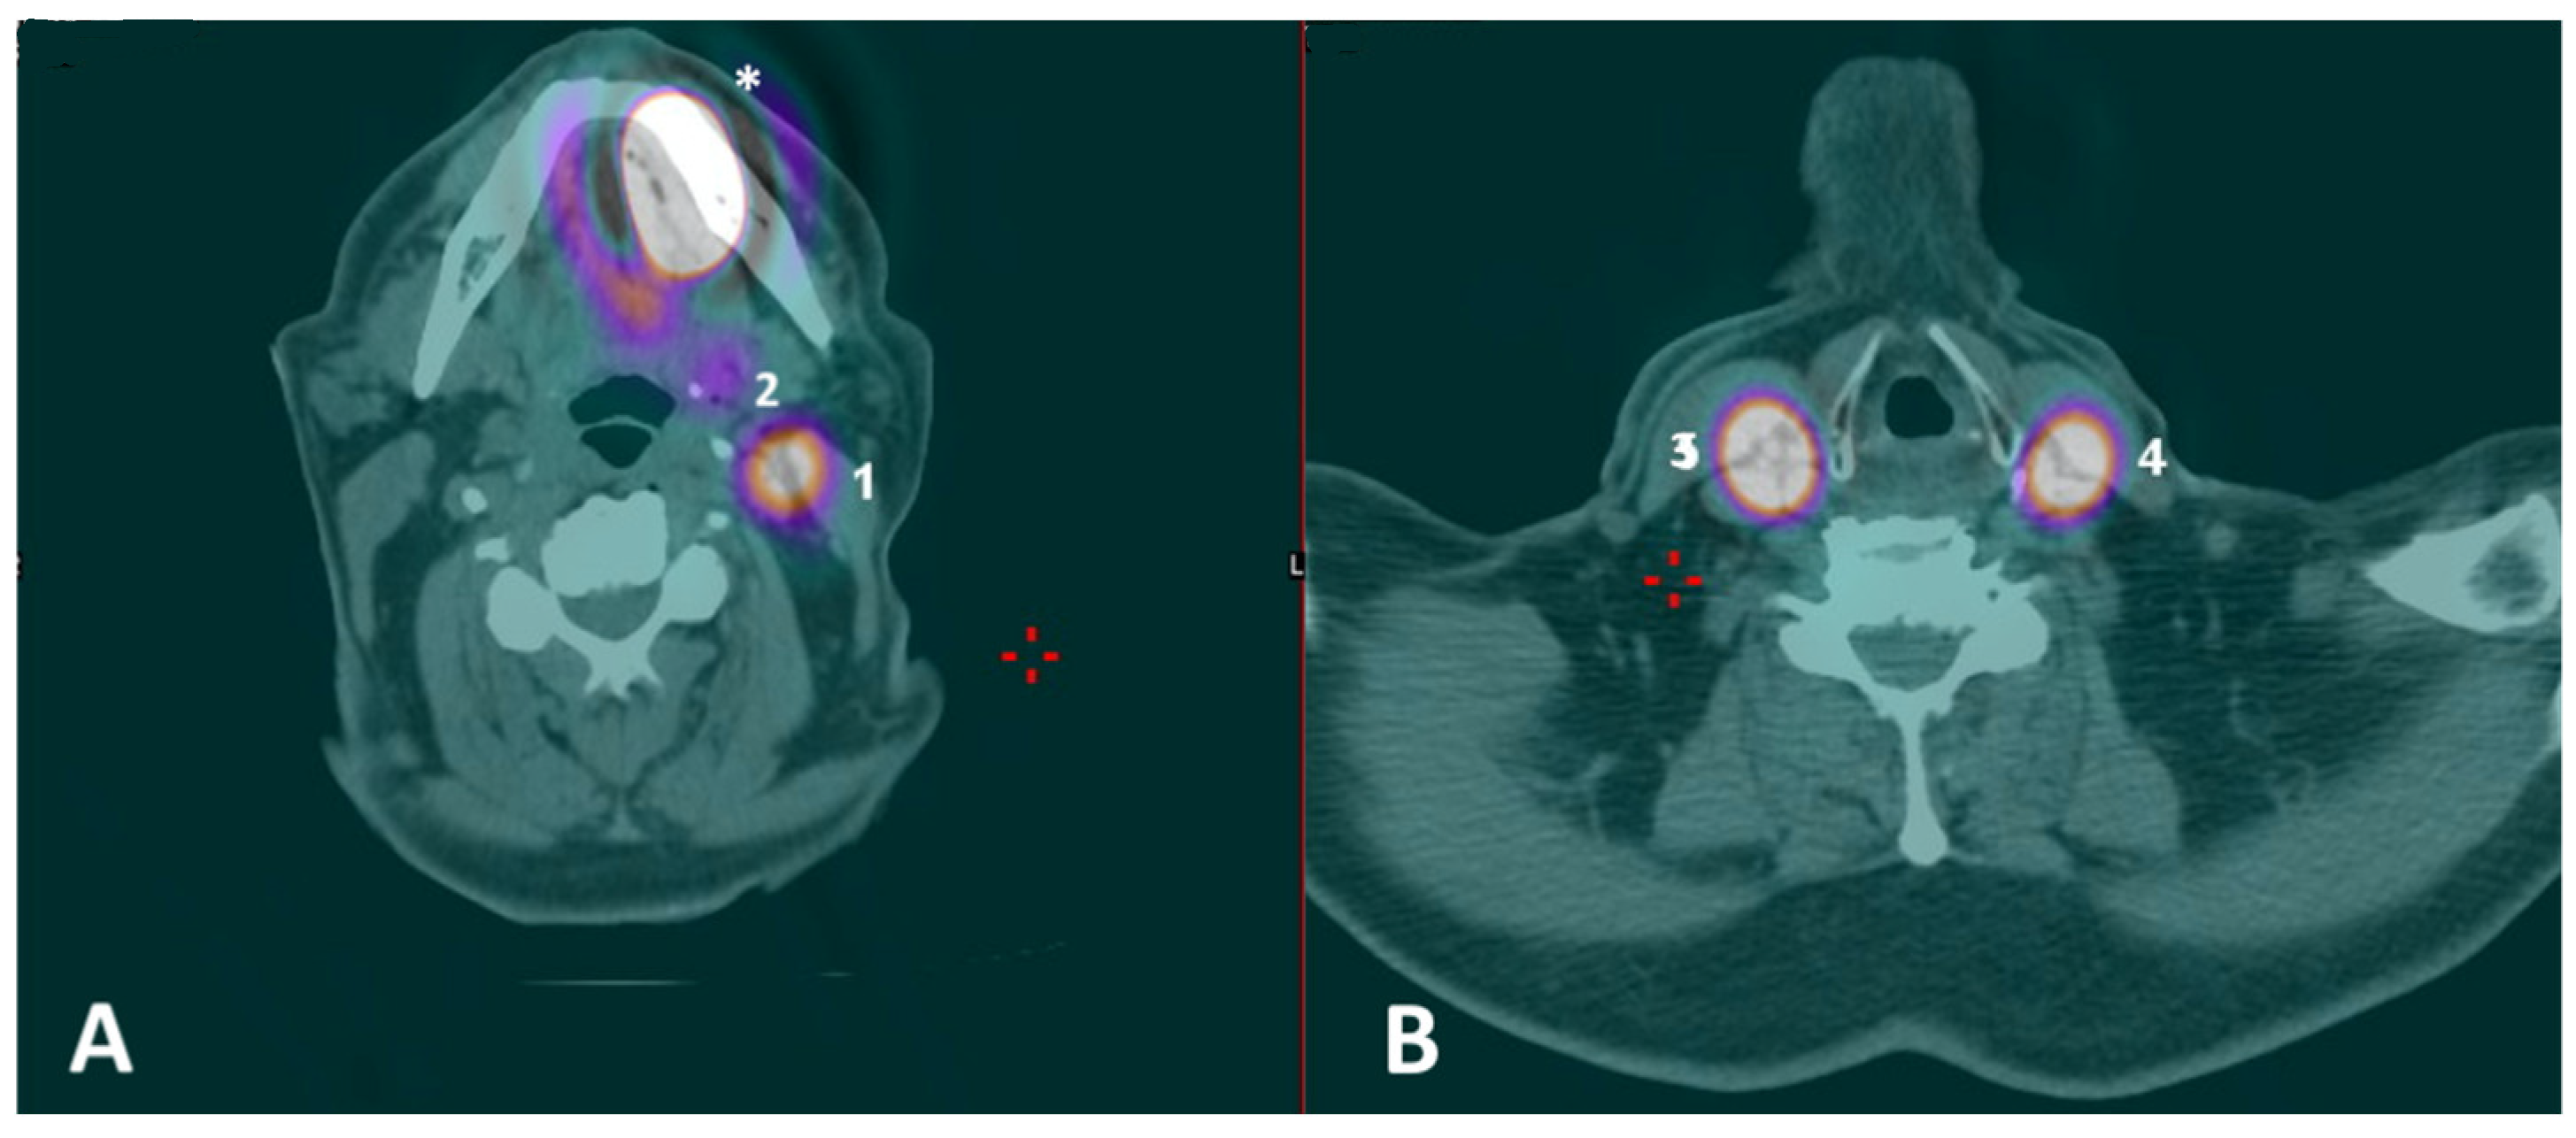

A 71-year-old man with a histologically proven left ventral tongue margin cT1 cN0 squamous cell carcinoma (SCC) was submitted to this protocol after a thorough radiological assessment (head and neck contrast-enhanced magnetic resonance imaging, neck ultrasound) had excluded obvious lymph node metastasis (Video S1). A preoperative lymphoscintigraphy with 99mTc-Tilmanocept (Lymphoseek®, Navidea Biopharmaceuticals, Inc.; Dublin, OH, USA) was performed about 4 h before surgery, with four submucosal injections around the tumor using an insulin syringe with a 27-gauge needle (0.1 mL per injection, 0.4 mL of total dose, 18 MBq) at cardinal points in healthy mucosa (Figure 1). Immediately after radioisotope injection, planar lymphoscintigraphic images were obtained using a GE Millennium gamma camera, with a high-resolution collimator. A support under the shoulders was positioned to reproduce operative conditions. The acquisition window was set at 140 Kev (±10%); the planar image matrix was 256 × 256. The images were obtained in anterior and posterior views. In addition, we performed single-photon emission computed tomography/computed tomography (SPECT/CT) to provide tomographic acquisition and improve anatomical SLN location. Dynamic acquisition allowed differentiation of the first lymph node relays (proper SLN(s)) from secondary ones: in this case, nodal hotspots were identified at levels IB, IIA and III on the left side and at level III on the right side (Figure 2). Skin landmarking was performed at the end of procedure to aid surgical planning.

The combination of 99mTc-Tilmanocept with ICG in a single, hybrid tracer is not yet approved for clinical use by the FDA/EMA. Therefore, the proposed ICG fluorescence-guided SLNB protocol with 99mTc-Tilmanocept used as a radiotracer seems a viable “surrogate”, which is designed to overcome these specific issues. In particular, a multimodal, stepwise approach is advised: after 99mTc-Tilmanocept injection, preoperative SPECT/CT can identify the specific nodal hotspot(s) and, thus, define the surgical “roadmap”; subsequently, a portable gamma probe is used to intraoperatively pinpoint the SLN location within each nodal hotspot, with high specificity but limited spatial resolution. Finally, a NIRF system takes advantage of the fluorescence emitted by the ICG to provide intraoperative, high-definition optical guidance within each nodal hotspot with higher spatial resolution, allowing the safe identification of a “hot” and “fluorescent” SLN (i.e., double control). Effective optical guidance may indeed strengthen the radioguidance, increasing the sensitivity of the whole procedure, especially in terms of spatial resolution [11]. This is of paramount importance in the so-called “shine-through areas”, in which a substantial reduction in the unnecessary dissection of para-SLN nodes can be achieved. This latter consequence may further reduce morbidity, mostly in the submandibular region, and aid pathologists in step-serial analysis by limiting the specimens provided. As stated above, although hybrid tracers do exist (i.e., ICG-99mTc-nanocolloid) and have been validated for this purpose [11], they still do not include Tilmanocept for radioguidance, which would be ideal for such a complex anatomical site as the anterior oral cavity. Indeed, the ability of Tilmanocept to identify hotspots, even at level IB, near the injection site, was also demonstrated in our small series (Figure 2), and in experienced hands, could help to avoid the systematic resort to the superselective dissection of “preglandular fat pad”, preserving the theoretical advantages of SLNB. Thus, the proposed multimodal protocol may mimic the use of a single, hybrid tracer with simultaneous optical and radioactive receptorial guidance.

Figure 2. (A,B) Preoperative SPECT/CT with identification of multiple nodal hotspots (lighter circular areas encircled by a purplish ring, or, for (2), the purplish region) at levels IB (2), IIA (1) and III (4) on the left side and at level III (3) on the right side; hotspot at the primary injection site was also visible (asterisk).